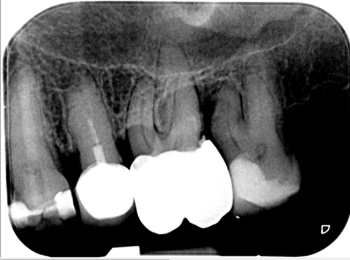

Röntgen Krone insuffizient

15: Krone insuffizient, apikale Aufhellung.

Röntgen Wuzelkanal

15: Zustand nach Revision und Behandlung des zweiten Wurzelkanals.